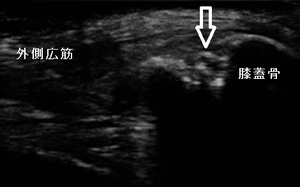

右膝外側 超音波長軸像 左同部 正常(健)側

その後、当接骨院を受診。右膝の上外側に圧痛、叩打痛、屈伸時痛が著明でした。超音波観察を行ったところ、

整形外科で「お皿の骨が分かれている」と言われたことが、有痛性分裂膝蓋骨であったことが分かりました。

(左上画像の矢印)

痛みのある状態を言います。男子は、超音波観察から膝蓋骨の上外側に診られるⅢ型と認められました。